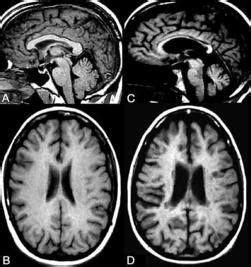

Let’s get straight to it. Primary Progressive Multiple Sclerosis (PPMS) is a less common, but significant, form of MS. Unlike the more well-known relapsing-remitting form (RRMS), PPMS is characterized by a steady and gradual worsening of neurological function from the onset of the disease. There are no distinct relapses or periods of remission. Think of it like a slow and steady climb, where symptoms continuously accumulate over time. This can make it particularly insidious because the progression is often less dramatic than a sudden relapse, but the cumulative effect can be just as, if not more, debilitating. For a long time, it was considered a more difficult form to manage because treatment options were limited, and the understanding of its underlying mechanisms was less developed. However, thanks to ongoing research and advancements in medicine, we’re gaining more insights and developing more targeted therapies. The key differentiator here is the progressive nature right from the start. This means that individuals diagnosed with PPMS experience a continuous decline in their abilities without the periods of recovery that people with RRMS might experience. This steady deterioration can impact various bodily functions, including mobility, balance, vision, and cognitive abilities, making daily life a constant adaptation. The diagnostic criteria for PPMS are also specific, often requiring evidence of continuous neurological worsening over a period of at least six months, confirmed by MRI scans showing specific types of lesions.

So, what are the tell-tale signs of Primary Progressive Multiple Sclerosis (PPMS) ? The symptoms can be quite varied because MS, in general, can affect almost any part of the central nervous system. However, in PPMS, the hallmark is that gradual worsening of function over time . Common early symptoms often include: mobility issues such as leg weakness, stiffness, or difficulty walking; balance problems leading to unsteadiness and falls; fatigue , which is a pervasive symptom across all MS types; bladder and bowel dysfunction ; and sometimes, visual disturbances like blurred vision or double vision. Unlike RRMS, these symptoms don’t typically appear suddenly in a distinct relapse; instead, they tend to emerge slowly and steadily worsen. Cognitive changes, such as problems with memory, attention, and processing speed, can also occur. The diagnosis of PPMS requires a thorough neurological examination, a detailed medical history, and evidence of disease activity on MRI scans. Specifically, doctors look for lesions (areas of inflammation and damage) in the brain and spinal cord that are characteristic of MS. To confirm the progressive nature, there needs to be evidence of continuous neurological worsening over a minimum period, usually at least six months. This distinction is crucial because it differentiates PPMS from other forms of MS. The diagnostic journey can sometimes be lengthy and challenging, as the insidious onset of PPMS symptoms can be mistaken for other neurological conditions. It’s essential for individuals experiencing these symptoms to seek medical attention promptly and work closely with a neurologist specializing in MS. Early and accurate diagnosis is vital for initiating appropriate management strategies and accessing support services. The variability of symptoms means that diagnosis can be particularly tricky, as the initial signs might be subtle and easily dismissed as normal aging or other minor ailments. However, persistent and worsening symptoms, especially those related to motor function and balance, should always be investigated.